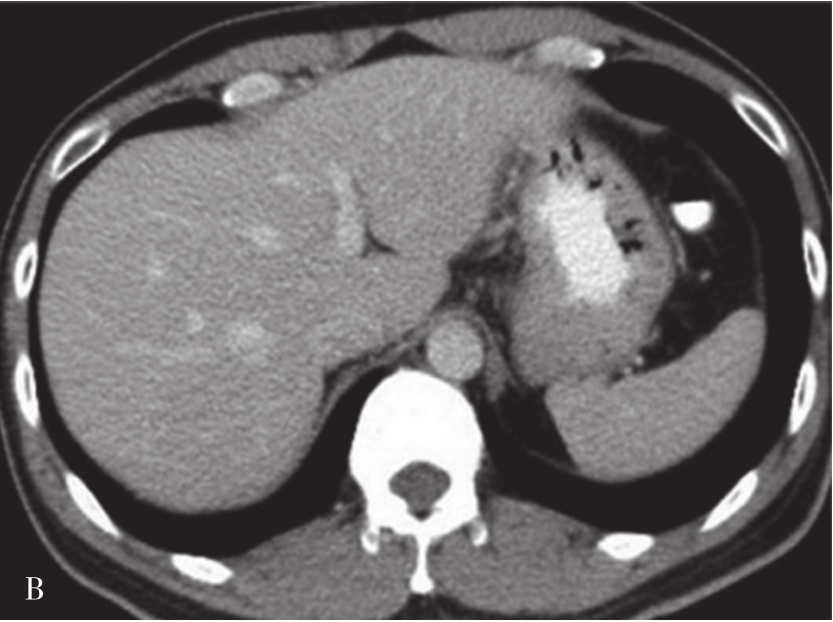

肝硬化是一种由多个病因引起的肝脏弥漫性病变,其特征为弥漫性的肝纤维化、细胞坏死、变性伴假小叶及再生结节形成。因此,肝硬化确诊的必备条件是肝的纤维化和再生结节。

(1)肝脏大小和形态:

肝脏内的脂肪浸润及肝硬化再生结节使得肝脏体积增大,中、晚期肝硬化由于纤维组织增生又使得肝脏体积缩小,以肝裂增宽为主,胆囊窝扩大,肝脏表面呈波浪状改变。通常肝右叶缩小明显,而尾状叶及左叶则可出现代偿性的增大(图5-21-37)。

图5-21-37 CT增强扫描门静脉期图像

可见肝脏形态异常,肝裂增宽,肝叶比例失调,肝脏体积缩小,肝包膜增厚,肝脏边缘呈波浪状改变,门静脉主干管径增宽,直径约1.8cm。脾脏体积明显增大,脾静脉增粗,同时可见食管胃底静脉曲张(箭头),肝周、脾周可见弧形液性密度影

(2)肝脏密度:

肝硬化产生的纤维化、再生结节使得密度增高,肝细胞坏死及脂肪浸润使肝组织密度减低,局部脂肪组织浸润可出现局灶性的密度减低区。

(3)继发性改变:

包括门静脉高压所引起的脾肿大,腹水和食管胃底静脉曲张等。